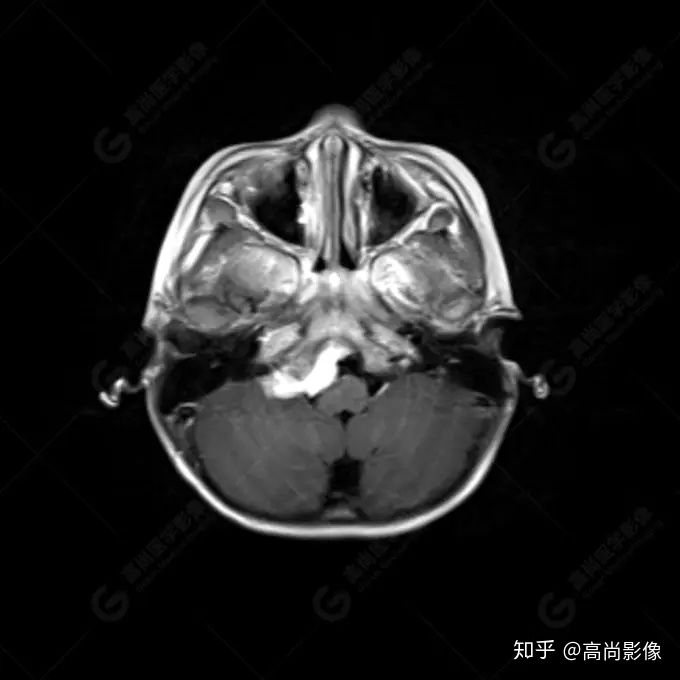

右側(cè)顳葉腫瘤切除術(shù)后(具體不詳):右側(cè)顳部骨質(zhì)不連續(xù)呈術(shù)后改變,右側(cè)顳葉術(shù)區(qū)見片狀長T1長T2信號影,F(xiàn)LAIR呈低信號;術(shù)區(qū)后方右側(cè)顳枕葉見一巨大占位性病變影,邊界欠清,大小約6.2×5.8×4.3cm(前后×左右×上下),信號不均勻,T1WI呈等稍低信號間雜少許高信號,T2WI呈高稍低混雜信號,DWI示部分病灶彌散受限,相應(yīng)ADC圖減低,磁敏感序列見部分呈極低信號,增強(qiáng)掃描可見明顯不均勻強(qiáng)化,鄰近硬腦膜及小腦幕增厚并明顯強(qiáng)化;另延髓右前方及右側(cè)橋小腦角區(qū)見一不規(guī)則形異常信號影,大小約3.2×1.3×3.7cm(左右×前后×上下),呈長T1稍長T2信號,F(xiàn)LAIR呈等信號,DWI未見受限,增強(qiáng)后明顯均勻強(qiáng)化,鄰近腦膜明顯強(qiáng)化。鄰近腦實質(zhì)及右側(cè)顳角明顯受壓;左側(cè)大腦半球未見局灶性信號異常,中線結(jié)構(gòu)稍左移。